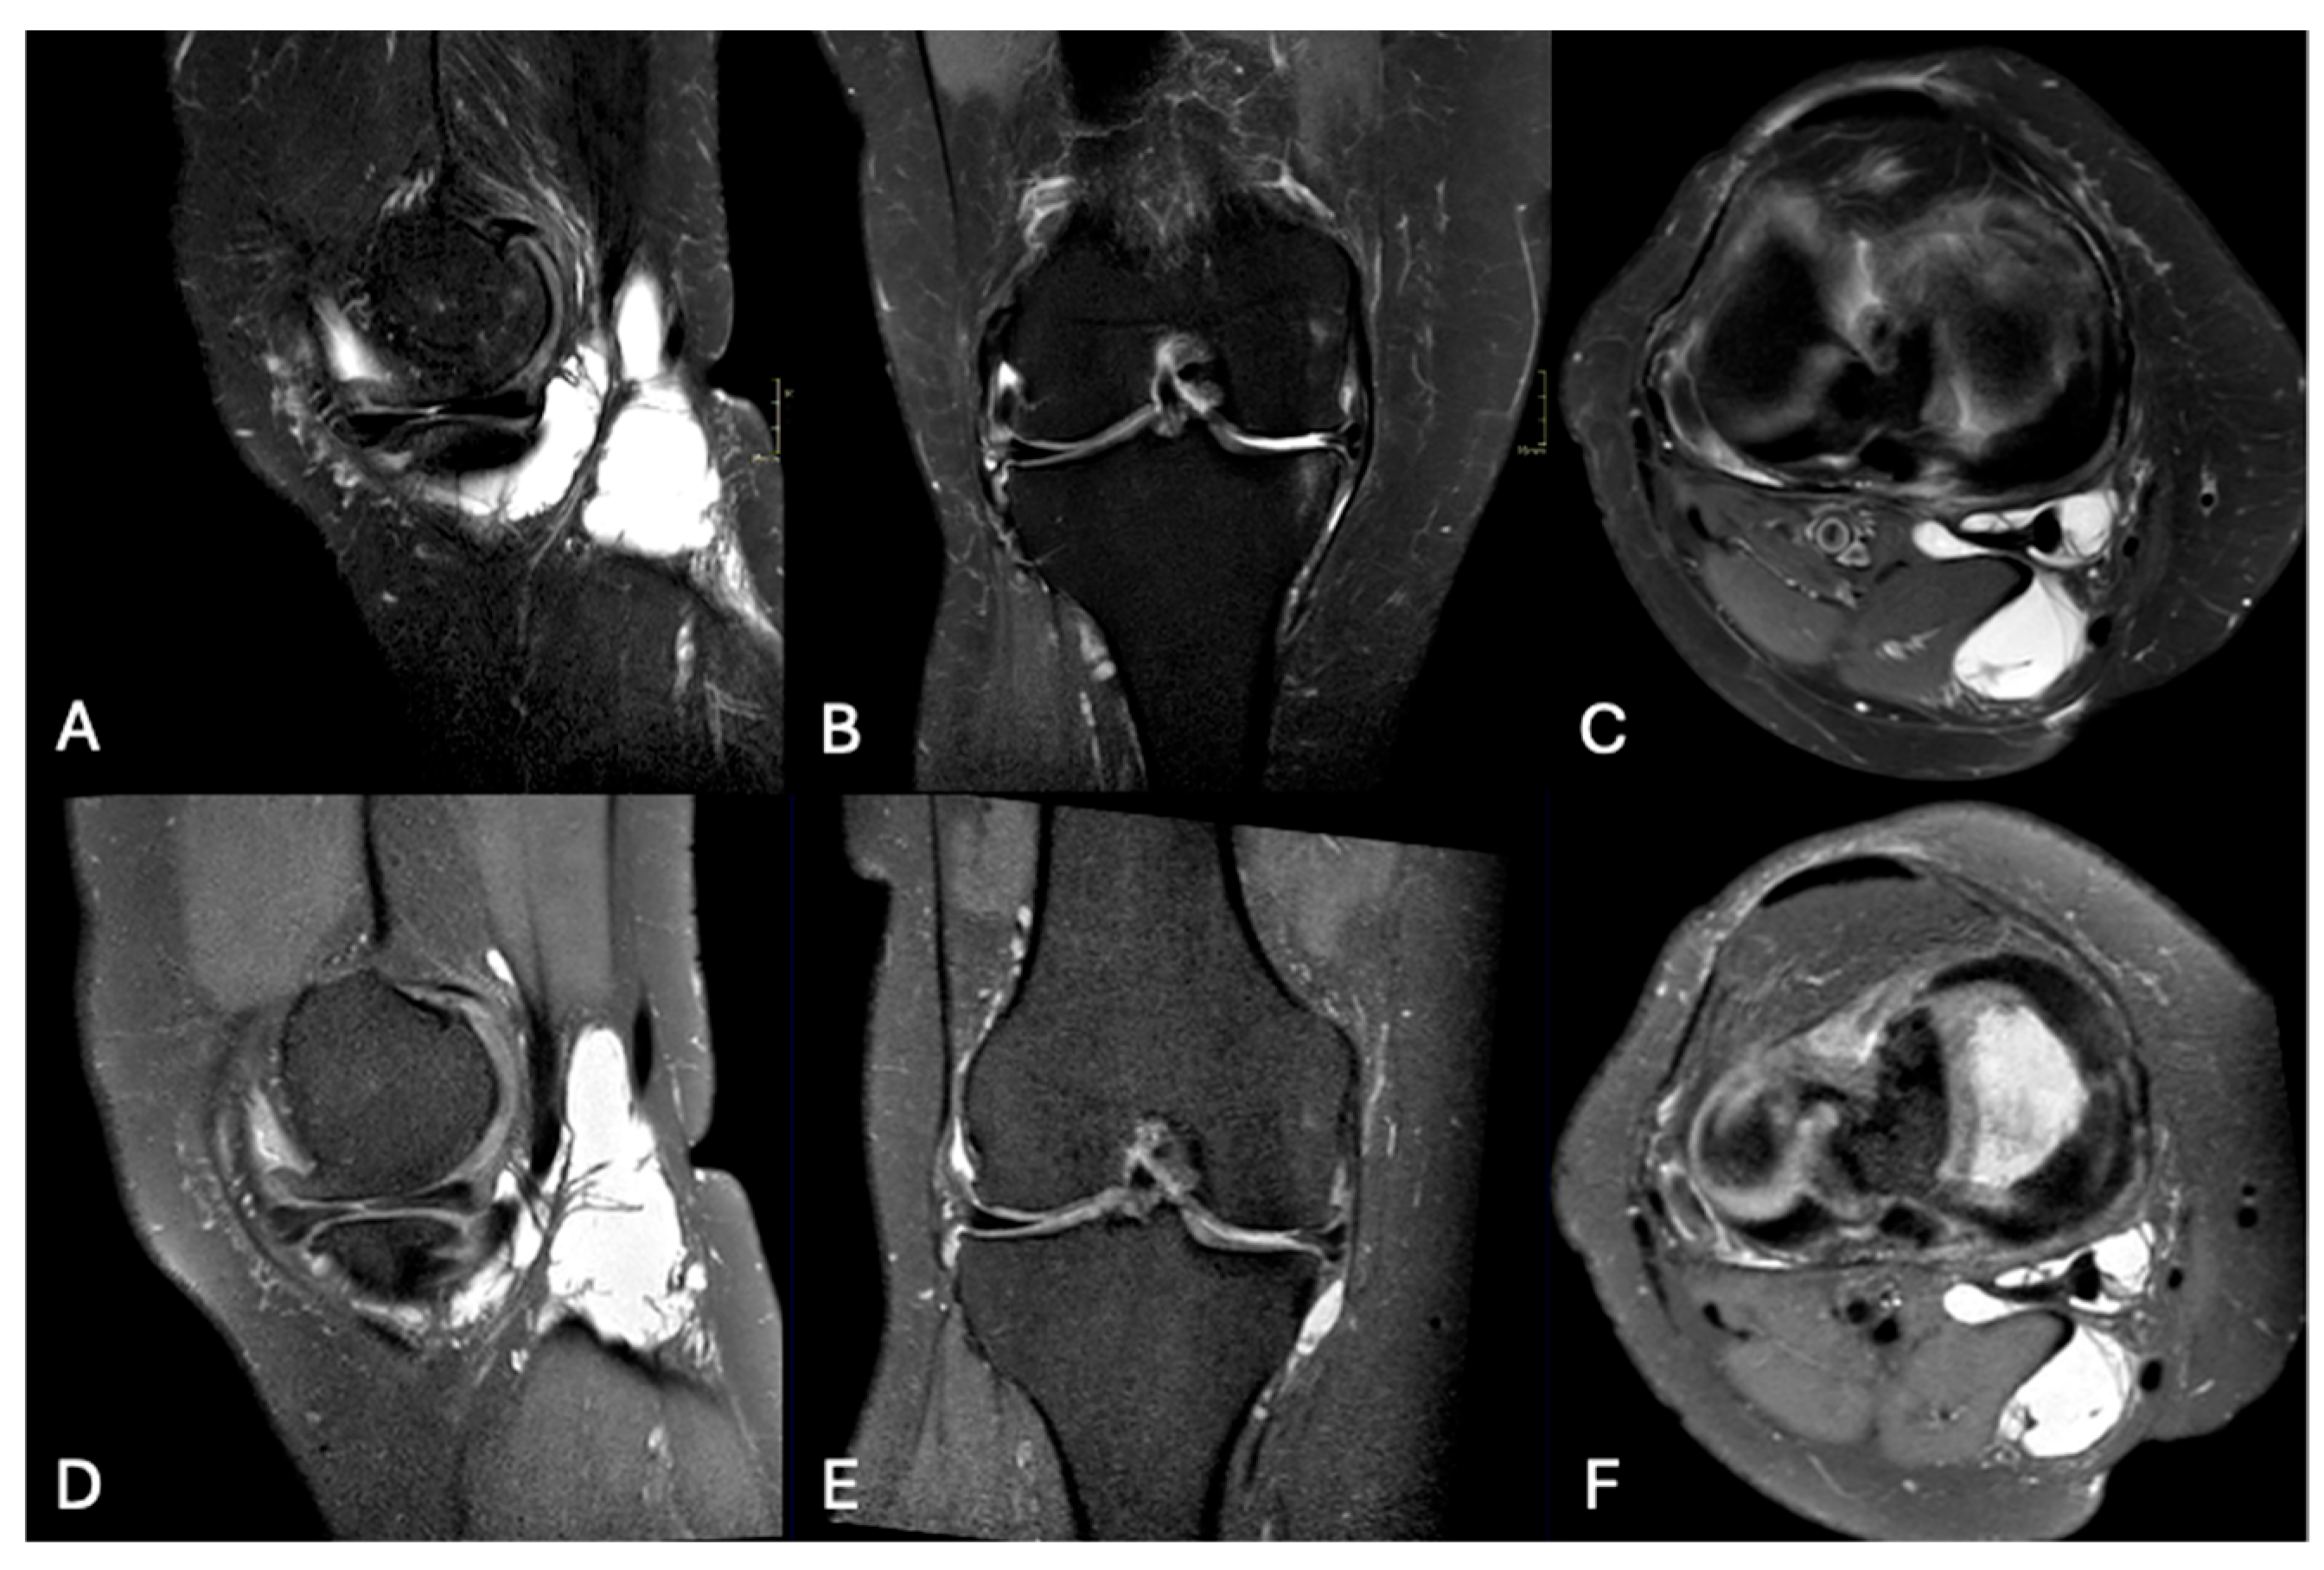

3.3. Pathological Entities

4. Discussion

| Medial meniscal tear (n, %) | 27 (35.5) | 37 (48.7) | < 0.001 |

| Lateral meniscal tear (n, %) | 12 (15.8) | 17 (22.4) | < 0.001 |

| Femoropatellar chondropathy (n, %) | 44 (57.9) | 40 (52.6) | 0.620 |

| Tibiofemoral chondropathy (n, %) | 35 (46.1) | 37 (48.7) | 0.500 |

| Bone edema (n, %) | 38 (50) | 39 (51.3) | 0.977 |